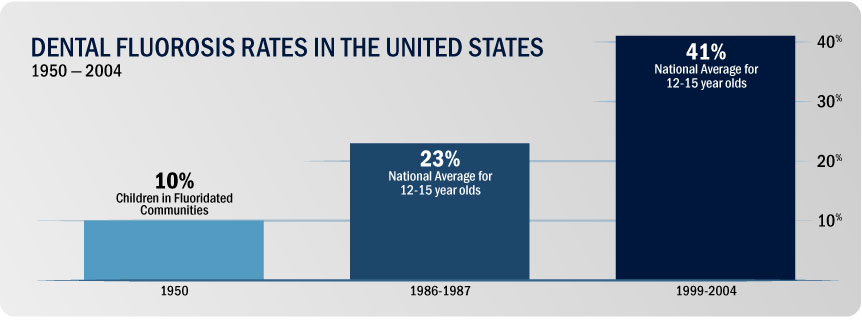

When a large amount of fluoride is consumed between birth and 8 years of age, the permanent teeth can be at risk of Dental Fluorosis. These changes range from barely visible lacy white markings to pitting in teeth. The CDC suggests to keep this in mind when making formula for infants, as frequent use of fluoridated tap-water in formula could cause Dental Fluorosis.

The damage to teeth and bones is not the only possible health effect. In July of 2012, a team of Harvard researchers published a “meta-analysis” of 27 studies that have investigated the relationship between fluoride and human intelligence. (Choi 2012) The overwhelming majority of these studies found that fluoride exposure was associated with reduced IQ in children.